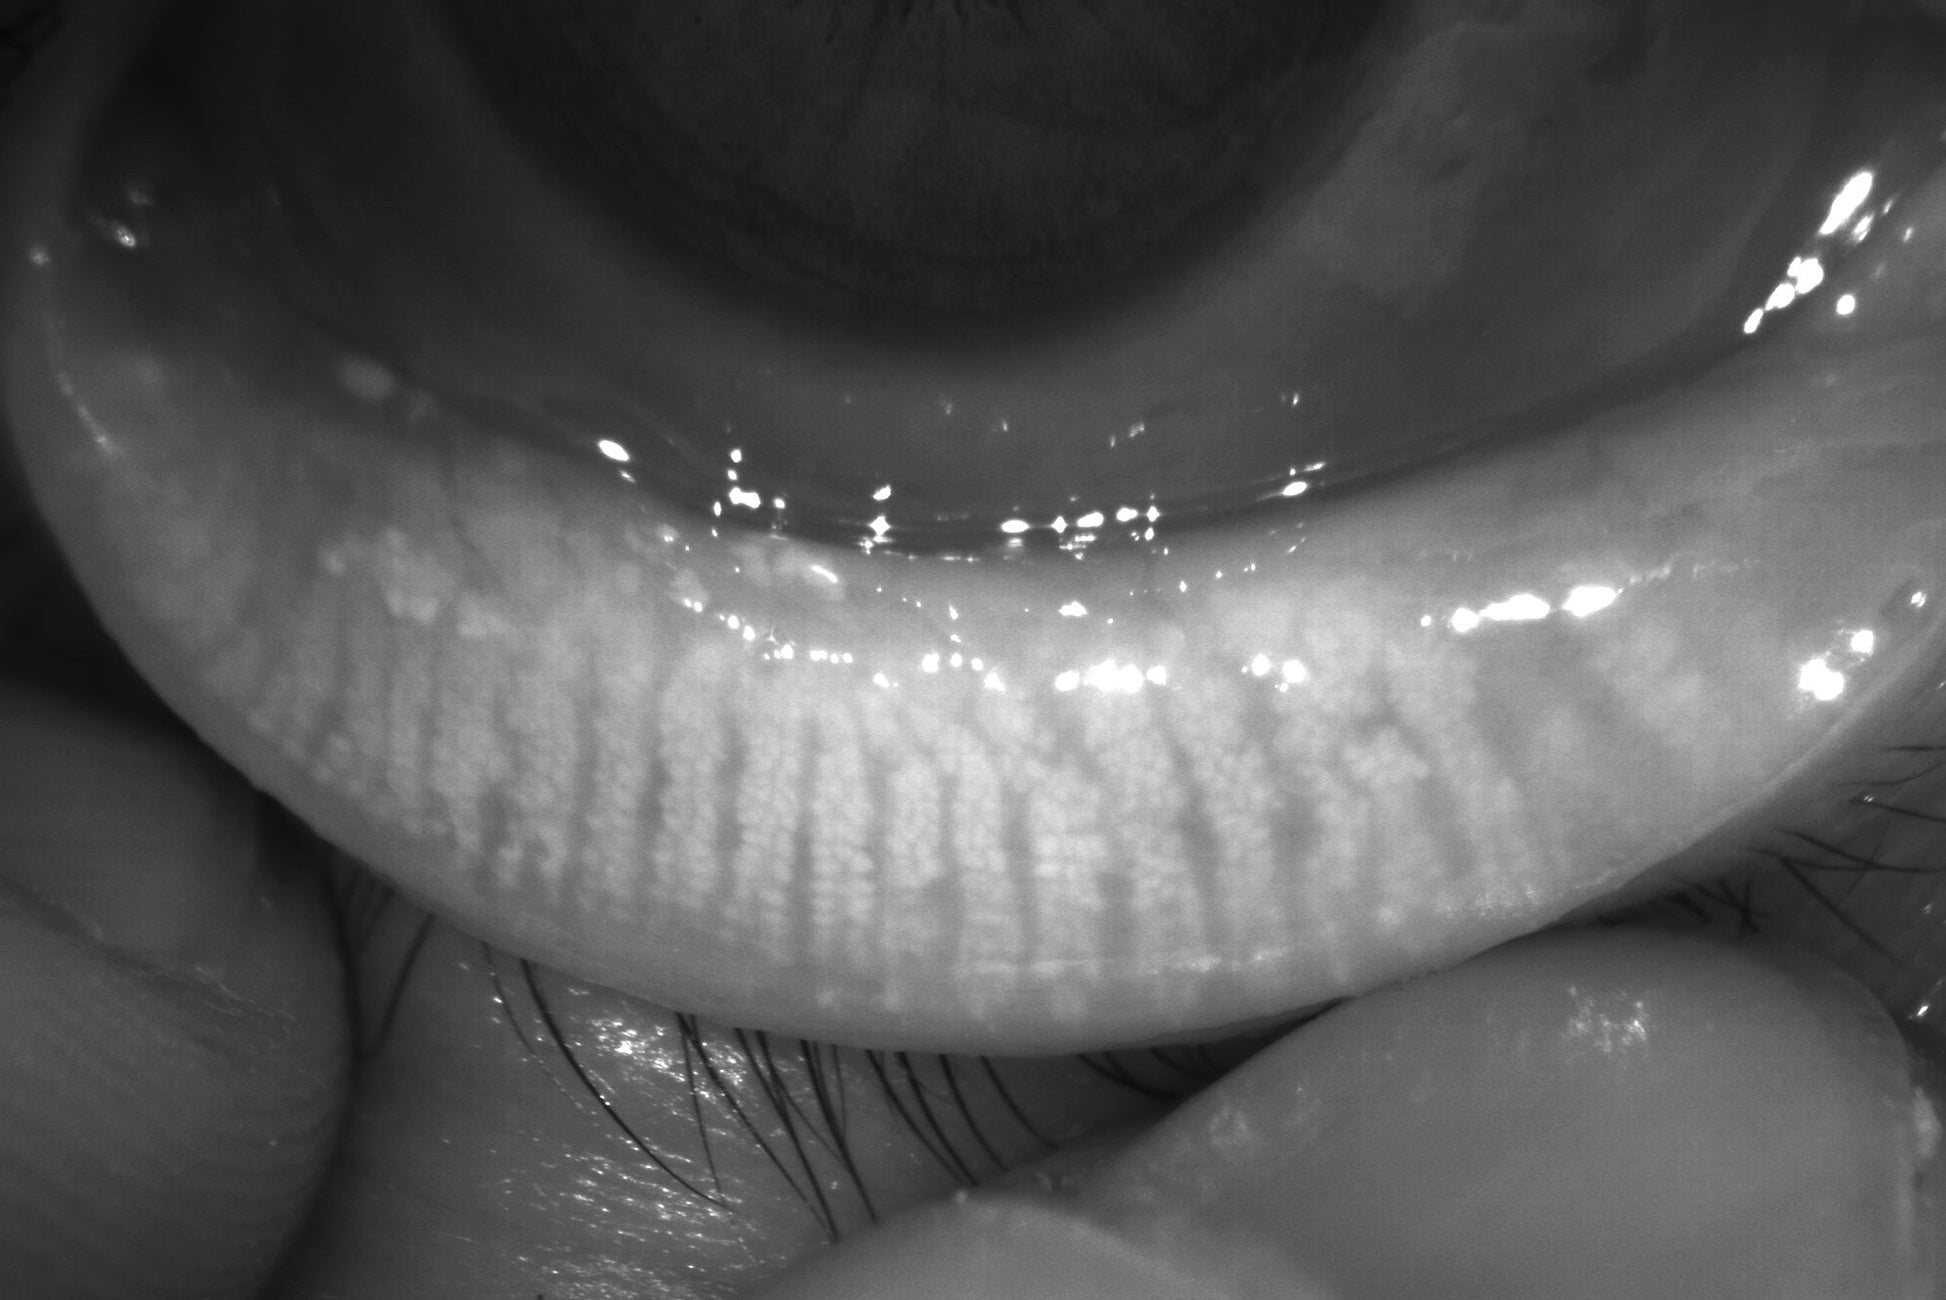

3. Gland Opening - gland opening measurement refers to assessing the orifices or ducts of the meibomian glands, which are located along the edges of the eyelids. Measuring the state of the gland openings helps in diagnosing conditions like meibomian gland dysfunction, this test can also be used for color meibography.